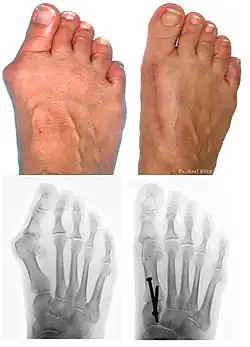

Traditional bunion surgery can be performed under local, spinal or general anesthetic. A person who has undergone bunion surgery can expect a 6- to 8-week recovery period during which crutches are usually required to aid mobility. An orthopedic cast is much less common today as newer, more stable procedures and better forms of fixation (stabilizing the bone with screws and other hardware) are used. Hardware may even include absorbable pins that perform their function and are then broken down by the body over the course of months. After recovery long term stiffness or limited range of motion may occur in some patients. Visible or limited scarring may also occur for patients.